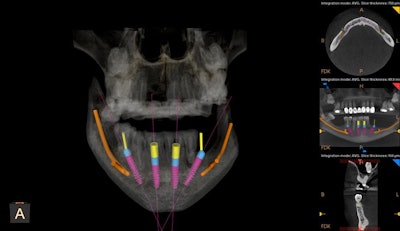

In the digital images below, you can see where CBCT technology and its associated treatment planning software allow us to "remove obstacles" by treatment planning angled implant placement and to "avoid obstacles" by treatment planning a prosthetic appliance that will decompress the inferior alveolar vein (IAV) nerve bundle. When combining a CBCT system with an intraoral scanner (CS 3700, Carestream Dental), I gain even more confidence in implant planning by merging a 3D scan with a digital impression for a prosthetic-driven approach to implants.

Mitra Sadrameli, DMD, states that treatment planning in 3D also allows for the consideration of greater specific patient-related information, resulting in surgical plans (and ultimately prosthetics) that are personalized for the patient.3 Consider the highly impacted maxillary molars that are evident in the above CBCT scans. A report from a maxillofacial oral radiologist (which I recommend with every scan) confirms that even though these are positioned superior to the level of the apices of the second molars, there is visual evidence that they are still in bone and present with no obvious pathologies, so they don't need specific treatment at this time. Periodic follow-up to evaluate stability of the impacted teeth may be considered.